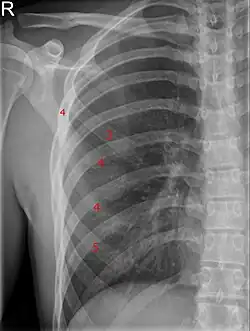

| Bifid rib at the right side seen on chest radiograph. The fourth rib splits in two towards the sternal end. | |

A bifid rib is a congenital abnormality of the rib cage and associated muscles and nerves which occurs in about 1.2% of humans. Bifid ribs occur in up to 8.4% of Samoans.[1] The sternal end of the rib is cleaved into two. It is usually unilateral.[2]

Bifid ribs are usually asymptomatic, and are often discovered incidentally by chest X-ray. Effects of this neuroskeletal anomaly can include respiratory difficulties, neurological difficulties, limitations, and limited energy from the stress of needing to compensate for the neurophysiological difficulties. An unstable bifid rib may lead to slipping rib syndrome.[3]